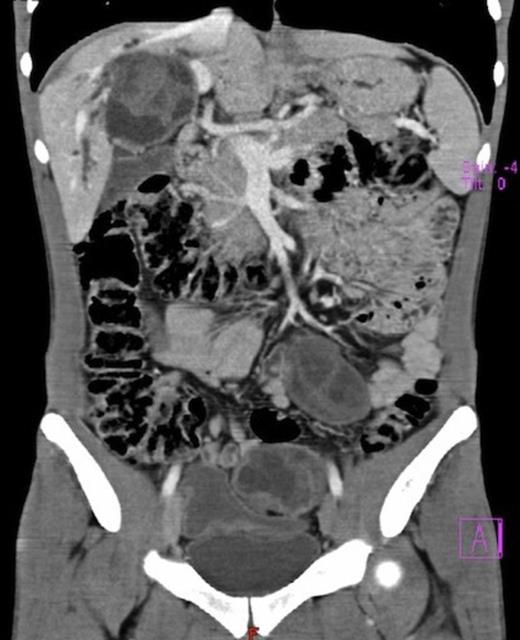

Surgical exploration confirmed the numerous peritoneal hydatid cysts and identified more lesions in the larger omentum (ranging from 3-12 cm) (Fig. 3). They were all resected, and a splenectomy was performed to remove completely the hilum cyst (Fig.4). Hydatid disease of the liver was massive, except in segments 1, 2 and 3. A cyst developing in segment 7 (7 cm) invaded the diaphragm and another voluminous cyst of 12 cm occupied the entire segment 8. A cyst of 8 cm in segments 4 and 5 involved the hepatic confluence, with destruction of the right hepatic duct and promoting a major biliary fistula with the left hepatic duct, confirmed by intra-operative transcystic cholangiography. The left hepatic duct near the hilar plate was included in the pericystic wall near segment 3. This cyst was chemically inactivated using iodopovidone (20 minutes), evacuated and followed by a thorough exploration of the cavity, which showed multiple biliary fistulae from the right sectorial hepatic ducts and a large defect in the left hepatic duct (Fig. 5). An extended right hepatectomy (segments 4 – 8), partial resection of the diaphragm and partial resection of the left hepatic duct including the fistula was performed. Reconstruction of biliary continuity was assured by a hepaticocholedocostomy, over a T-tube (Fig. 6). Confirmation of sectorial left hepatic ducts patency was done by intra-operative cholangiography.